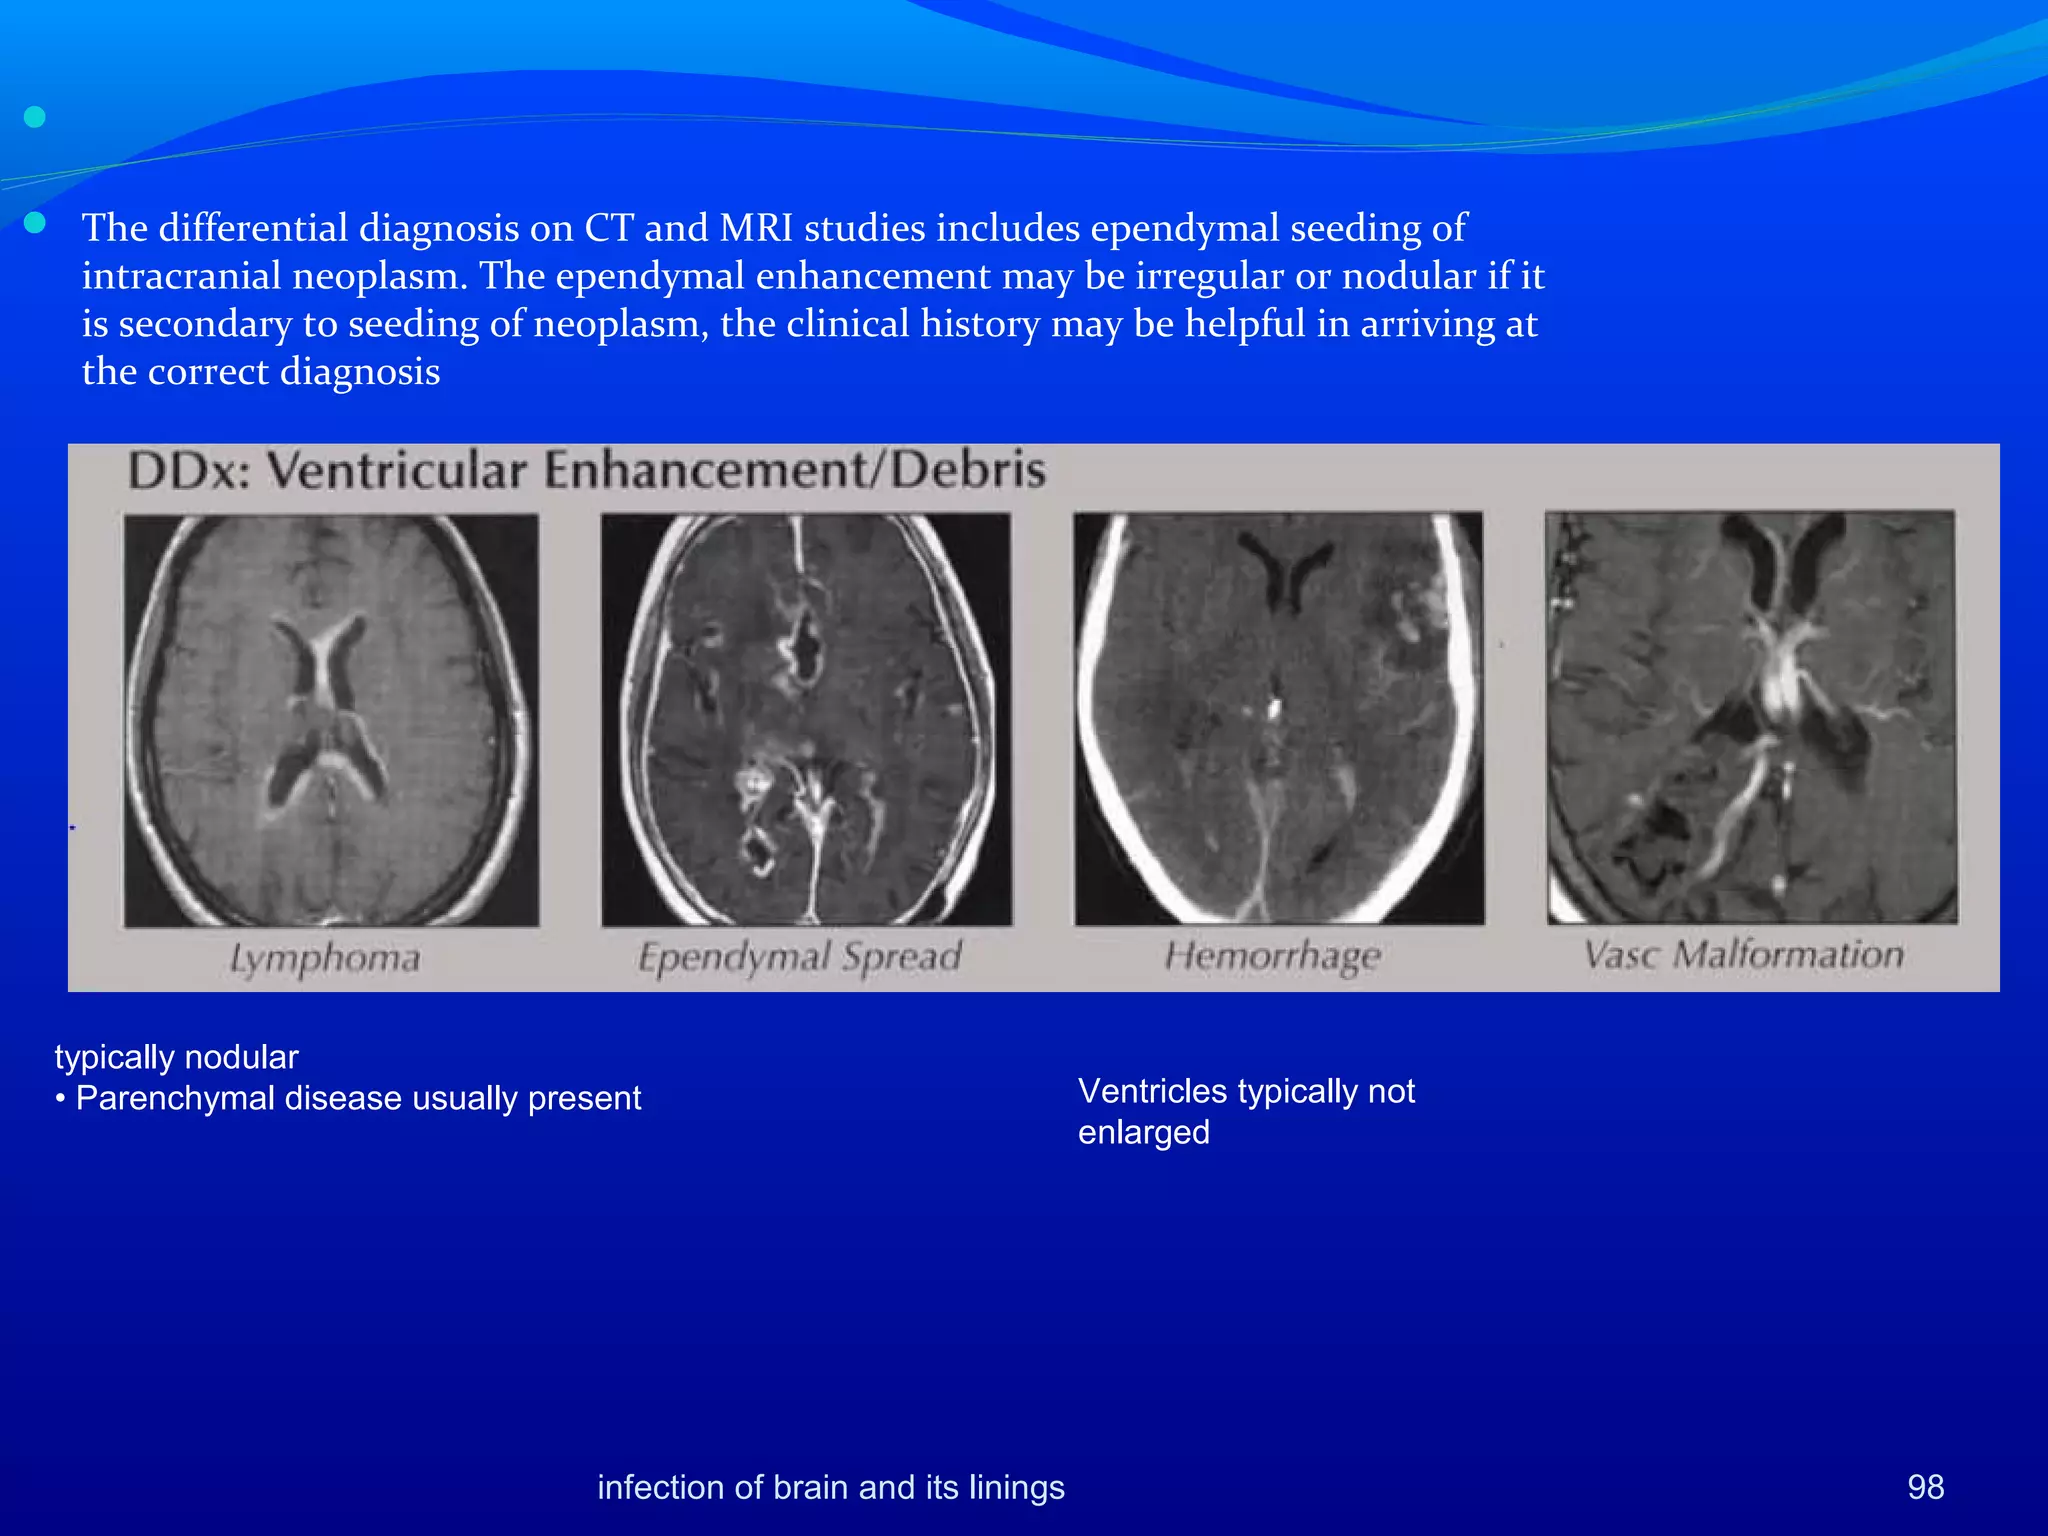

Ependymitis

 Ventriculitis, or ependymitis, is an

inflammation of the ependymal lining of

the ventricular system

 rupture of periventricular abscess or

from retrograde spread of infection from

the basal cisterns by way of the fourth

ventricle

 Hydrocephalus may result from

intraventricular adhesions and septation

caused by organization of intraventricular

exudate and debris, resulting in blockage

of the interventricular foramina.

 A trapped fourth ventricle may result

from obstruction of its outlets and the

aqueduct because of ependymitis

infection of brain and its linings 96

 NECT scan -normal or may

show only slightly increased

density in region of affected

ependyma

 MRI -marginal ventricular

abnormality or only slightly

increased signal intensity in

the region of affected

 proton-density-weighted

images. The fluid within the

ventricles may show slightly

increased intensity,.

 Contrast-enhanced CT or MRI

studies show uniform, thin

ependymal enhancement

Gadolinium-enhanced MRI

studies show thin, smooth

ependymal enhancement in an

AIDS patient with

cytomegalovirus ependymitis.



 The differential diagnosis on CT and MRI studies includes ependymal seeding of

intracranial neoplasm. The ependymal enhancement may be irregular or nodular if it

is secondary to seeding of neoplasm, the clinical history may be helpful in arriving at

the correct diagnosis

typically nodular

• Parenchymal disease usually present Ventricles typically not

enlarged